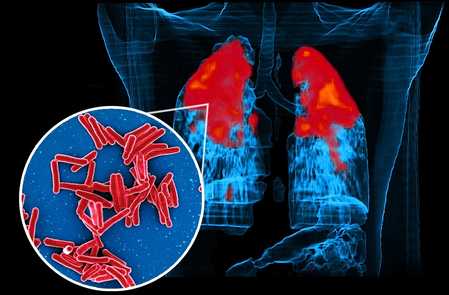

New Delhi, Dec 3 (IANS) The bacteria Mycobacterium tuberculosis, which causes the world’s most infectious disease Tuberculosis (TB), can survive antibiotic treatment and live longer by changing their outer fat coating, according to a new study led by researchers from the Indian Institute of Technology (IIT) Bombay on Wednesday.

In the study, published in the Chemical Science journal, the researchers showed that the key to the bacteria’s drug tolerance lies in their membranes — complex barriers made mostly of fats, or lipids that protect the cell.

While the active bacteria had loose, fluid membranes, the dormant ones had rigid, tightly ordered structures, indicating its defence mechanism.